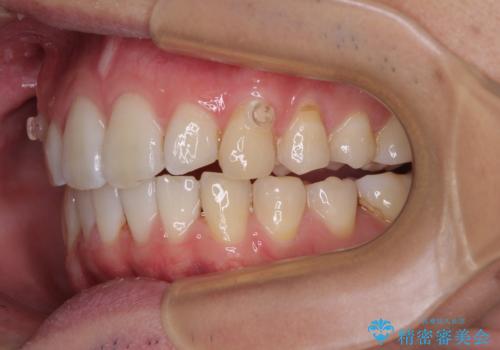

前歯のデコボコをインビザラインで綺麗に改善

- 上下前歯のデコボコとクロスバイトを気にして来院された患者様です。

インビザラインを用い、IPR(歯と歯の間を削る)と歯列全体を拡大させることで、歯並びを整えていくこととしました。

毎日22時間の装着時間を徹底してくださったのですが、左右ともに臼歯が咬合しなくなるという、インビザライン独特の症状が強く長く続いてしまい、終了するまでに長期間を要してしまいました。